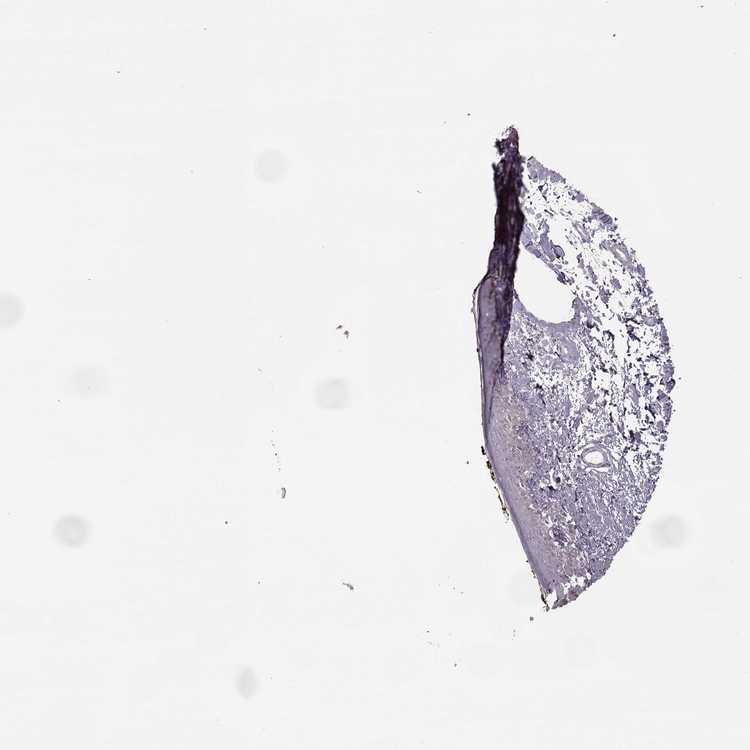

SKIN 1 - Antibody stainingi

Antibody staining in the annotated cell types in the current human tissue is reported as not detected, low, medium, or high, based on conventional immunohistochemistry profiling in selected tissues. This score is based on the combination of the staining intensity and fraction of stained cells.

Each image is clickable and will lead to virtual microscopy that enables deeper exploration of all samples and also displays staining intensity scores, fraction scores and subcellular localization as well as patient and tissue information for each sample.

Antibody HPA023908

Langerhans Not detected

Fibroblasts Not detected

Keratinocytes Not detected

Melanocytes Not detected